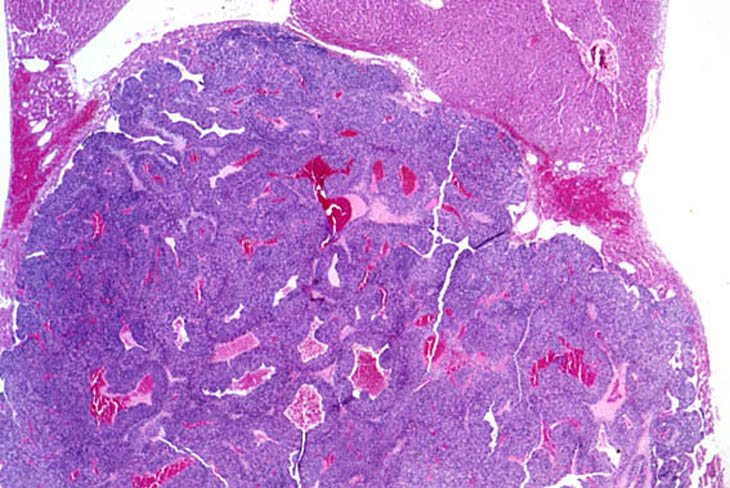

A basophilic hepatoblastoma is arising within a discrete hepatocellular adenoma.